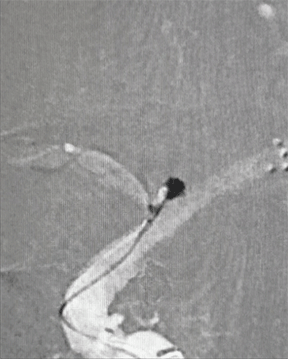

颅脑DSA-3D成像

临床诊断:右侧大脑中动脉分叉部宽颈动脉瘤;右侧大脑中动脉狭窄支架植入术后。

动脉瘤尺寸:2.12*1.95mm

患者动脉瘤瘤颈累及M1分叉部中、下两个干支;且患者阵发性头痛加重,动脉瘤破裂出血的风险较高,需要手术干预。该动脉瘤属相对宽径,单纯弹簧圈栓塞,弹簧圈易脱出,需支架辅助。病人选择支架辅助弹簧圈栓塞治疗技术。

患者一期治疗使用Neuroform EZ支架重塑右侧大脑中M1狭窄段,但支架远端定位落于中干,紧邻动脉瘤开口处,故封堵动脉瘤瘤颈的支架只能穿过第一枚支架的网孔释放于下干支。